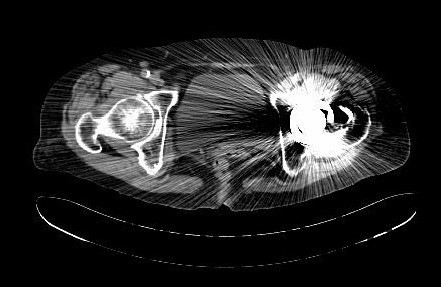

查体:专科:左髋部后外侧陈旧手术瘢痕,左髋关节前方压痛、无轴向叩击痛阴性,无大转子叩击痛,双下肢感觉及血运均正常。双下肢肌力V级。动量:右髋内外旋诱发疼痛,屈曲90度疼痛。外旋明显滚动试验阴性,左髋4字试验阳性。双下肢等长。左髋关节屈90°,伸0°,外展40°,内收20°,内旋30°外旋10°。右髋关节屈120°,伸直0°,外展40°,内收20°,内旋30°外旋30°。 辅助检查:2010-12-08 ESR 6.0mm/h,2011-01-04外院CRP8.5mg/l(参考范围0-10mg/l)X线示左双动股骨头置换术后,假体松动、下沉,髓腔内可见骨水泥影。近端干骺端骨质明显缺损。髓腔内侧皮质形态不规则。

诊断:左双动股骨头置换术后假体松动、下沉、股骨骨缺损(PaproskyII型) 治疗:患者在全麻下左双动股骨头假体取出+同种异体骨植骨+左全髋关节翻修术,术后予以抗炎(二联)+抗凝+镇痛+护胃+补液等治疗,并予以抗骨质疏松药物